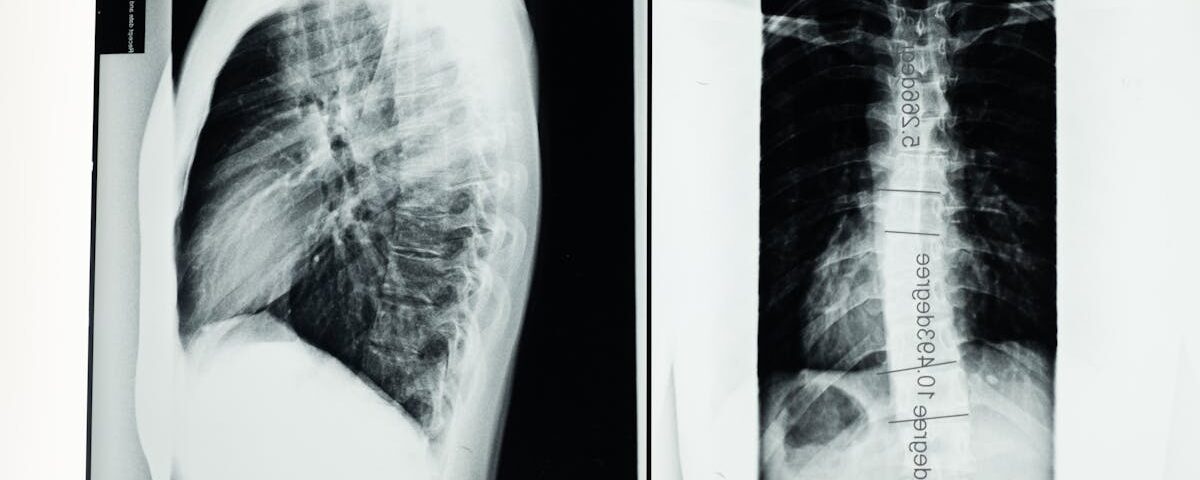

Qu’est-ce qu’une hernie discale?

Une hernie discale est une condition où le noyau d’un disque intervertébral se déplace et exerce une pression sur les nerfs environnants, causant douleur et inconfort.